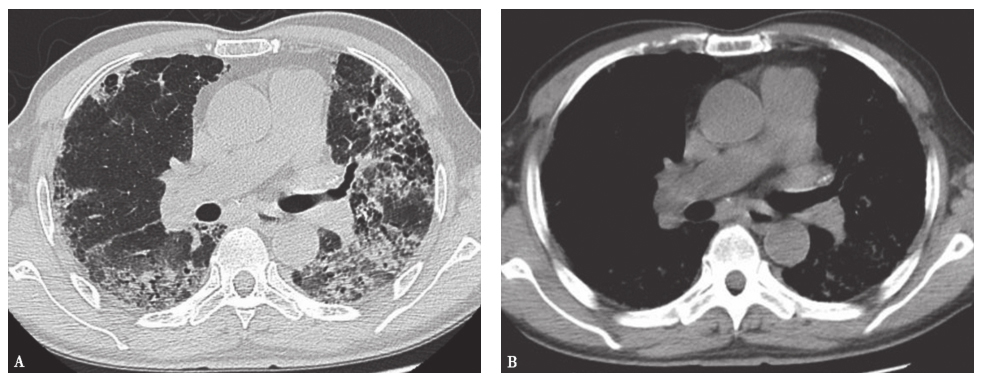

(1)特发性肺纤维化(IPF):是一种原因不明的慢性致纤维化性间质性肺炎,组织病理学表现为普通型间质性肺炎(usual interstitial pneumonia,UIP),病变局限于肺部。一般认为,环境刺激、病原体感染及自身免疫异常等均可成为本病的致病因子。IPF一般慢性起病,临床表现为干咳、呼吸困难等。其典型的HRCT改变表现为网格影,伴有斑片状改变,以外周和胸膜下分布为主,蜂窝样改变明显,并见牵拉性支气管扩张征象,磨玻璃影相对比较少见(图1)。肺功能表现为限制性通气功能障碍。典型IPF依据临床表现及典型HRCT改变即可诊断,不典型IPF需要肺活检病理明确诊断。目前IPF的治疗主要以吡非尼酮或尼达尼布为主,糖皮质激素或激素联合免疫抑制剂疗效不佳。

图1特发性肺纤维化胸部CT表现

男性患者,73岁,咳嗽伴气喘2年,加重1个月。胸部CT可见双肺弥漫间质性改变,小叶间隔和小叶内间隔增厚,病变主要分布于胸膜下,并见牵拉性支气管扩张伴蜂窝样改变。临床诊断为特发性肺纤维化